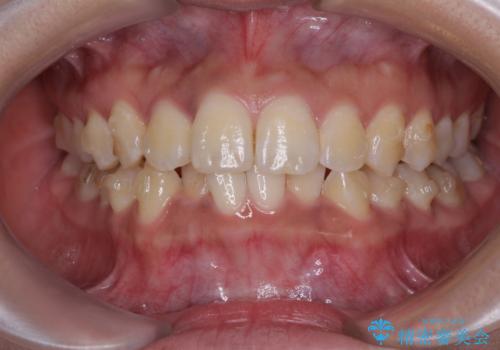

前歯のデコボコと隠れてしまう下顎前歯 インビザラインですっきりと改善

インビザライン発注後に長期滞在先から2年間ほど帰国することができず、インビザラインの有効期限内に終了できるのか不安でしたが、矯正治療開始後は十分な装着時間を達成され、1年未満の期間で無事に終えることができました。